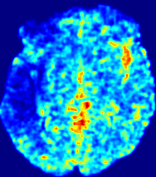

4.3.1 Advection Imaging via Advection-Diffusion

Slice #1Slice #2Slice #3Slice #4Slice #5Slice #6𝐕gt𝟐subscriptnormsuperscript𝐕gt2\|\bf{V}^{\text{gt}}\|_{2}Refer to captionRefer to captionRefer to captionRefer to captionRefer to captionRefer to caption𝐕est𝟐subscriptnormsuperscript𝐕est2\|\bf{V}^{\text{est}}\|_{2}Refer to captionRefer to captionRefer to captionRefer to captionRefer to captionRefer to captionRefer to caption1.51.51.51.21.21.20.90.90.90.60.60.60.30.30.30.00.00.0(mm/s)𝑚𝑚𝑠(mm/s)Destsuperscript𝐷estD^{\text{est}}Refer to captionRefer to captionRefer to captionRefer to captionRefer to captionRefer to captionRefer to caption0.0150.0150.0150.0120.0120.0120.0090.0090.0090.0060.0060.0060.0030.0030.0030.0000.0000.000(mm2/s)𝑚superscript𝑚2𝑠(mm^{2}/s)

Figure 14: PIANO identifiability testing: advection imaging via advection-diffusion. Top row shows 𝐕gt2subscriptnormsuperscript𝐕gt2\|{\bf{V}}^{\text{gt}}\|_{2} used for simulating ground truth pure advection. Rows below show the estimated 𝐕est2subscriptnormsuperscript𝐕est2\|{\bf{V}}^{\text{est}}\|_{2} and Destsuperscript𝐷estD^{\text{est}} on corresponding slices. Note that the plotted value scale for Destsuperscript𝐷estD^{\text{est}} is 0.01 of that for 𝐕gt2subscriptnormsuperscript𝐕gt2\|{\bf{V}}^{\text{gt}}\|_{2} and 𝐕est2subscriptnormsuperscript𝐕est2\|{\bf{V}}^{\text{est}}\|_{2}.

We use the same ‘Advection Imaging’ simulation of Sec. 4.2.1 as the concentration dataset for PIANO. However, instead of modeling pure advection (Eq. 15), we let PIANO estimate both velocity 𝐕estsuperscript𝐕est{\bf{V}}^{\text{est}} and diffusivity Destsuperscript𝐷estD^{\text{est}} via the advection-diffusion PDE (Eq. 2) underlying the proposed PIANO model. Fig. 14 shows the estimated 𝐕est2,subscriptnormsuperscript𝐕est2\|{\bf{V}}^{\text{est}}\|_{2}, and Destsuperscript𝐷estD^{\text{est}} fields for one patient. Although PIANO has the freedom to estimate both a velocity and a diffusivity field from pure advection, PIANO differentiates well between advection and diffusion: the estimated 𝐕est2subscriptnormsuperscript𝐕est2\|{\bf{V}}^{\text{est}}\|_{2} successfully reproduces the ground truth 𝐕gt2subscriptnormsuperscript𝐕gt2\|{\bf{V}}^{\text{gt}}\|_{2} governing the simulated advection process, just as it already did in the ‘Advection Imaging via Advection’ test (Fig. 12). More importantly, the estimated diffusivity Destsuperscript𝐷estD^{\text{est}} is orders of magnitudes smaller than 𝐕est2subscriptnormsuperscript𝐕est2\|{\bf{V}}^{\text{est}}\|_{2}, indicating the estimated diffusion is negligible compared to the estimated advection, which is highly consistent with the underlying pure advection of the simulated data.